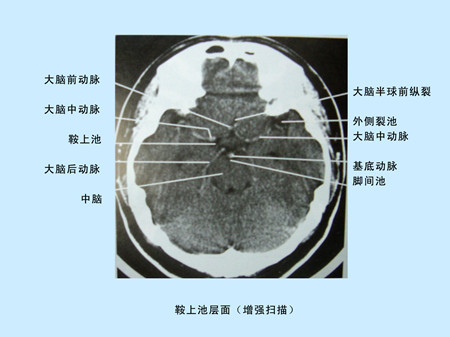

CT(Computed Tomography)是電子計算機X射線斷層掃描技術簡稱。CT的工作程序是這樣的:它根據(jù)人體不同組織對X線的吸收與透過率的不同,將測量所獲取的數(shù)據(jù)輸入電子計算機,電子計算機對數(shù)據(jù)進行處理后,攝下人體被檢查部位的斷面或立體的圖像,可發(fā)現(xiàn)體內(nèi)任何部位的細小病變。CT圖像是重建圖像。

CT平掃及增強掃描腦組織圖像顯示 超聲經(jīng)顱多普勒檢測時顯示圖像